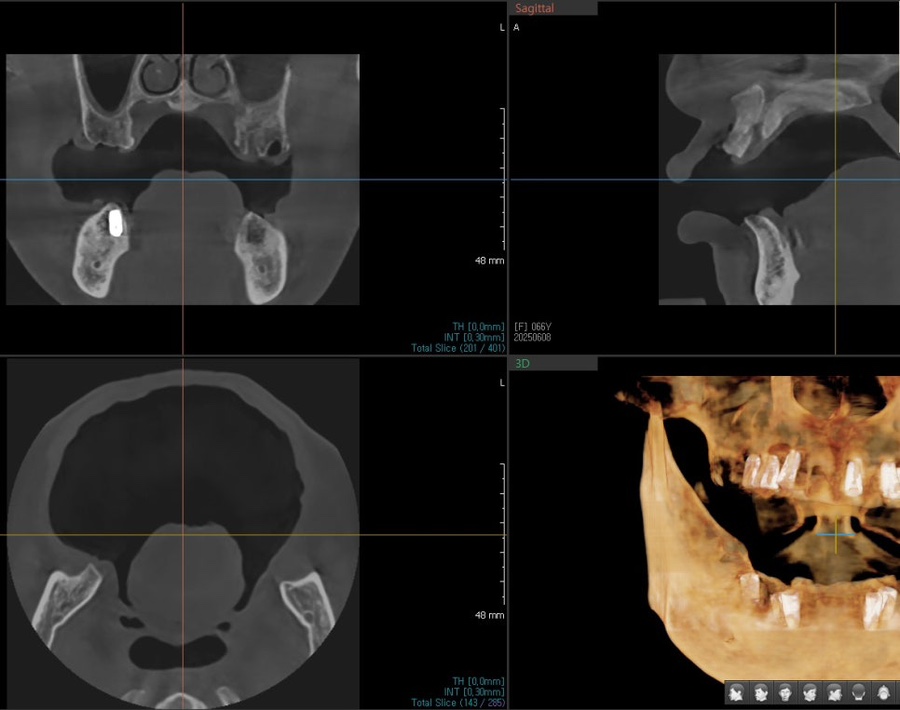

정밀 진단

저희 잠실 치과 서울오브치과병원에서는

시니어 환자분들도

3D 스캐너·구강내시경·교합 검사를 통해

현재 치아 상태를 세밀하게 확인하고 있습니다.

검사 결과,

앞니는 치질이 충분히 남아 있어

과도한 삭제 없이도 라미네이트가 가능했고,

잇몸 상태도 안정적으로 유지되고 있었습니다.

교합 또한 큰 문제 없이 맞물리고 있어

기존 보철물의 색과 형태만 개선해도

더 자연스럽고 균형 잡힌 앞니 라인으로

회복될 수 있는 케이스였습니다.